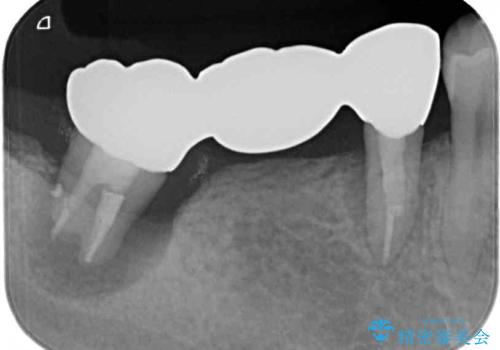

診察を行ったところ、手前の歯は歯根が破折しており、抜歯が必要な状態でした。

左右ともに臼歯部しか咬んでおらず、ブリッジの手前側の歯が破折したことで大きく揺さぶられてしまい、奥側の歯も周辺の歯が著しく吸収し、抜歯が必要な状態でした。

ブリッジの支台歯2本を抜歯し、反対側の咬合負担を軽減するために、通常よりも短い待機時間で2本のインプラントを埋入することとしました。